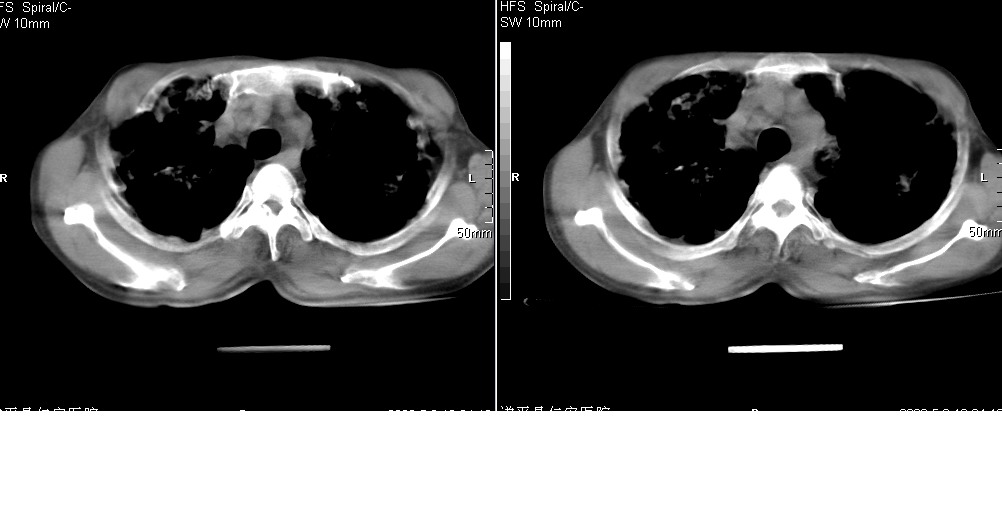

以下是引用光线在2008-5-6 18:36:00的发言:[br]双肺结核(左上肺空洞形成)、间质性改变合并感染,右肺大泡;右侧胸膜增厚。

以下是引用zsl6918在2008-5-7 1:54:00的发言:[br]首先肺泡蛋白质沉着症,其次考虑机遇性感染。